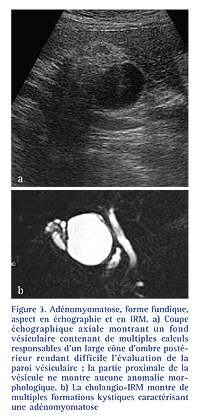

En IRM, l’aspect classique de l’adénomyomatoseconsiste en la présence demultiples images d’additions de signalliquidien au sein d’une paroi vésiculaireépaissie [6, 9] (Fig. 3). Cet aspectest particulièrement bien démontré surles séquences de cholangio-IRM. Lesimages kystiques intrapariétales sontle plus souvent en hyposignal T1 et enfranc hypersignal T2 mais peuventapparaître en hypersignal T1 du faitd’un contenu fait de débris ou d’unebile épaisse [9].